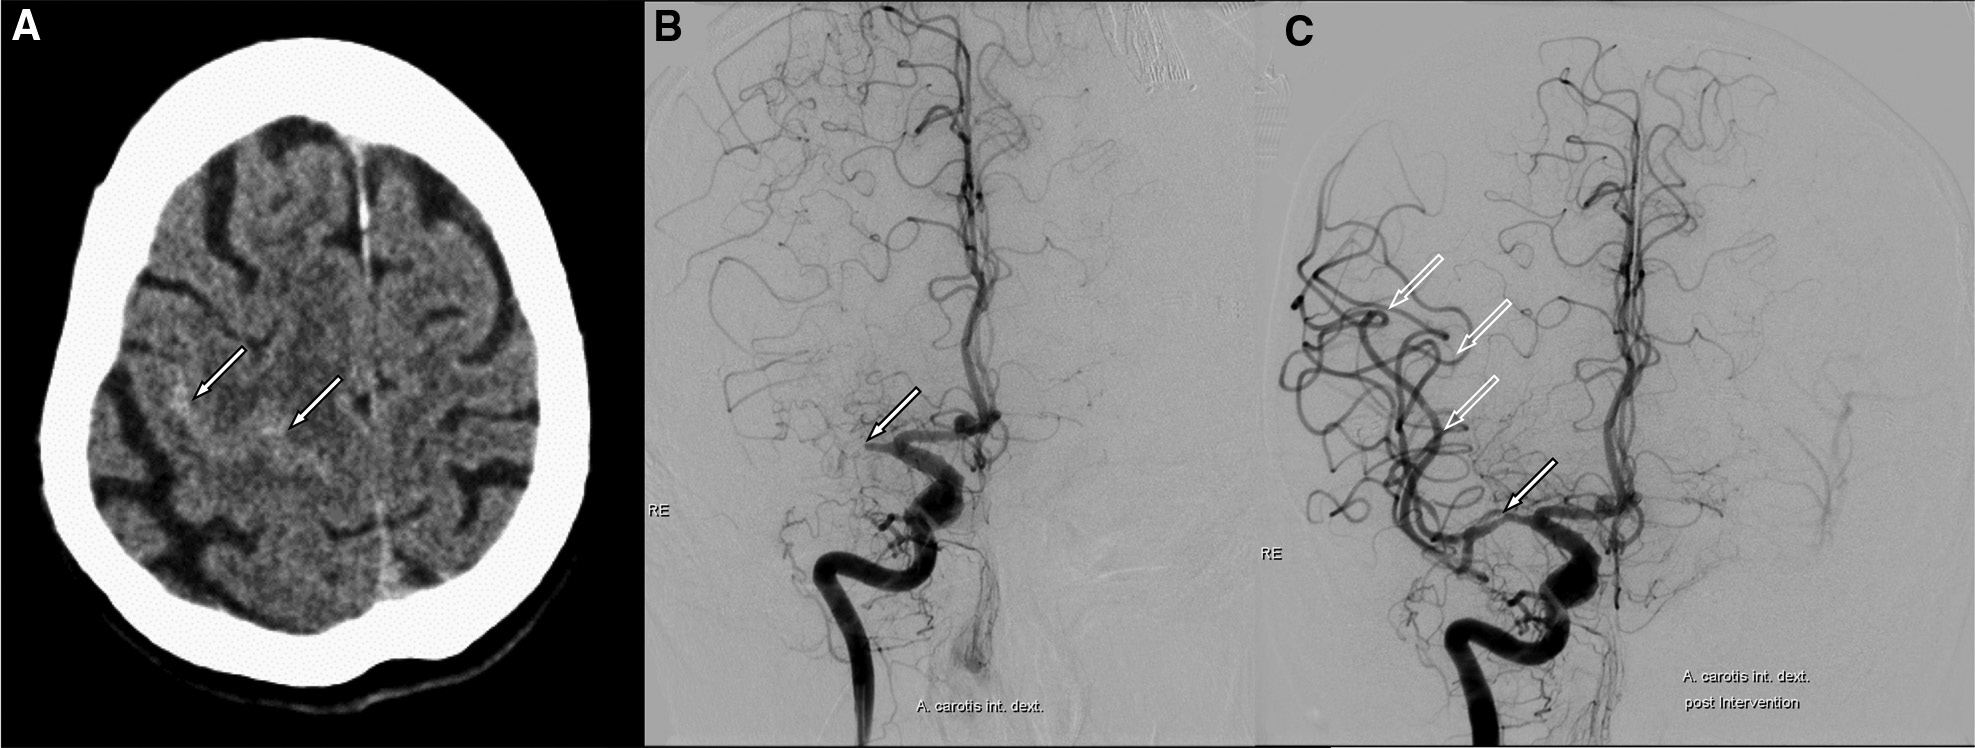

74岁,女性。

急性左侧偏瘫和忽视(NIHSS=12),无近期创伤史。

发病2小时CT显示右额凸面蛛网膜下腔出血(图1A)。CTA显示右侧大脑中动脉主干闭塞。随后,机械血栓切除术的治疗成功(图1B和1C)。

图1 发病2小时CT

术后磁共振成像显示边缘带梗死,并证实蛛网膜下腔出血无进展(图2)。临床结局非常好(3个月改良Rankin量表=1)。